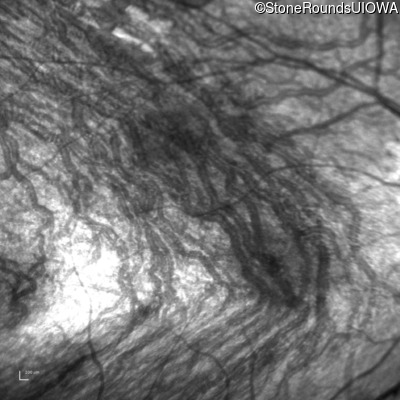

Infrared Fundus Photograph - Right - 10/300 sc

Exemplar